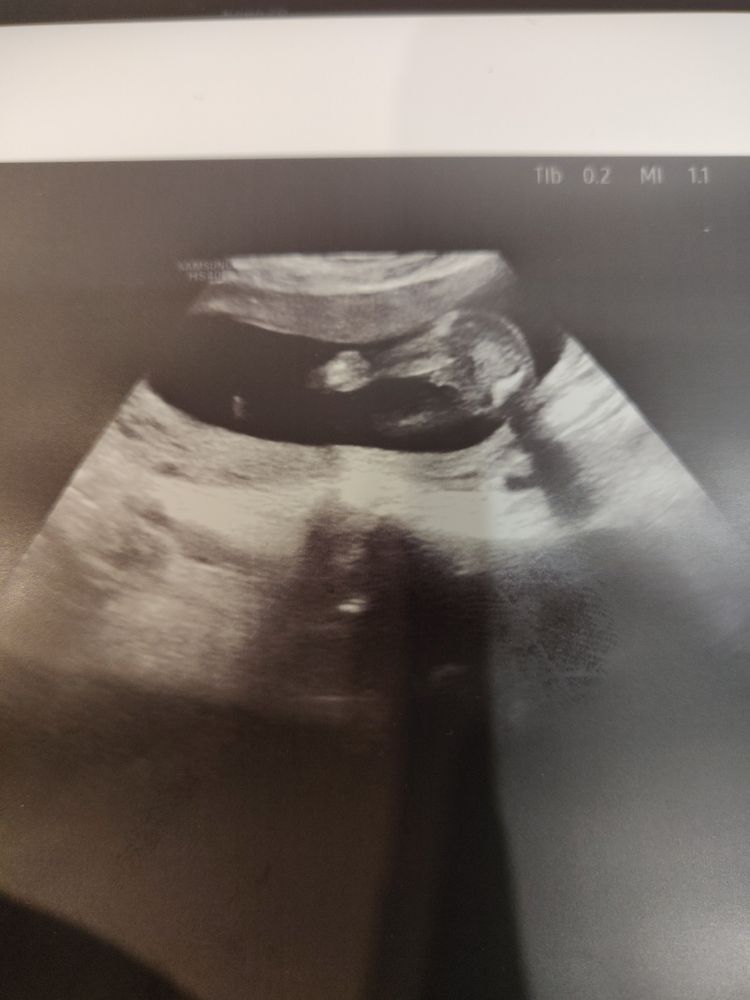

Девочки милые помогите!🤗🥺

Мальчишка) такую же картину сегодня видела)

Ну слушайте, я вижу уже стручок, у девули все-таки пирожочек там) Похоже, что мальчишка)

Тут точно пацан 😁

Alisa, точно))) мои мальчишки так же выглядели на узи 😁

Alisa, у меня 3 дочки ,сейчас сына жду ...поверьте у девочек такого меж ножек нет

Пацан, тут ни с чем не спутать мне кажется))))

Пфф.. у меня младший сын всю беременность ногой прижимал свое хозяйство так, что по УЗИ все ставили мне девочку)) Но у вас тут невооружённым взглядом видно, что молодой человек 💪

Да парень 100%💙 У девочек такого не бывает.

Мальчишка это. У девочек по-другому всё выглядит)